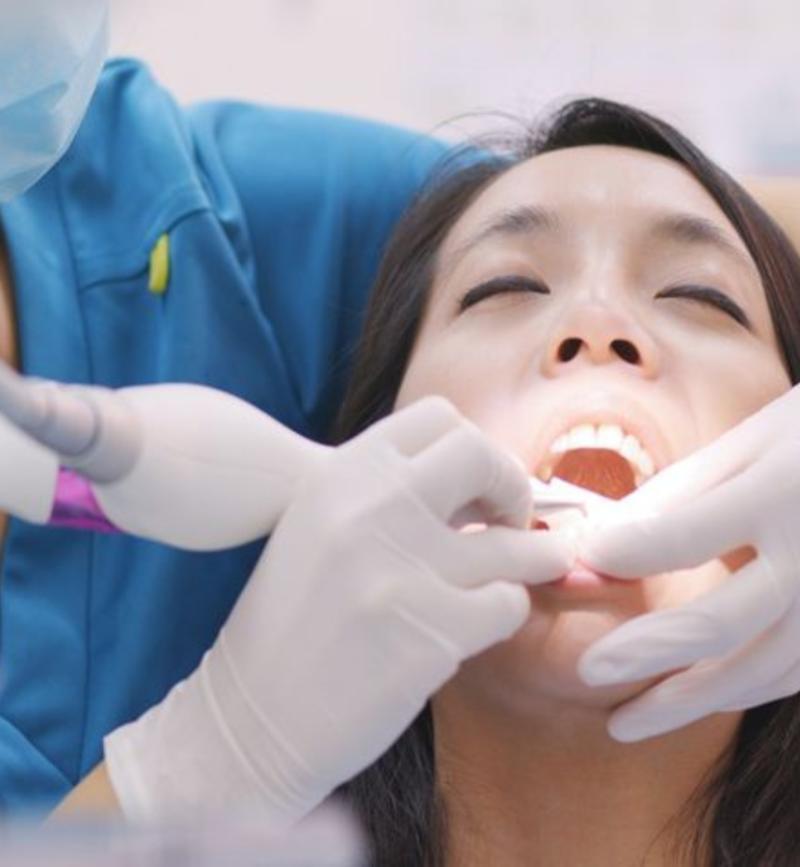

Ultrasonic scaling is an advanced dental cleaning technique that effectively removes plaque, tartar, and bacteria from your teeth and gums. Using high-frequency sound waves, this treatment ensures a deep and gentle clean, reducing the risk of gum disease and cavities. Ultrasonic scaling is painless, quick, and enhances overall oral hygiene by reaching areas that traditional cleaning methods might miss.

Ultrasonic scaling is a highly effective and gentle dental cleaning procedure that removes stubborn plaque, tartar, and bacteria from teeth and gums. Using high-frequency sound waves, it ensures a deep clean that reaches areas traditional cleaning methods might miss. This treatment helps prevent gum disease, bad breath, and cavities, promoting overall oral health.

Ultrasonic scaling is a professional dental cleaning procedure that uses high-frequency vibrations to remove plaque, tartar, and bacteria from your teeth and gums. This advanced technique helps prevent gum disease, cavities, and bad breath, ensuring optimal oral hygiene.

The effectiveness of Ultrasonic Scaling depends on the technology and techniques used. This procedure utilizes high-frequency vibrations and water irrigation to break down plaque and tartar, reaching deep into gum pockets for a thorough clean.